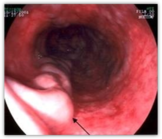

10. Езофагоскопія

Чітко видно варикознорозширену вену стравоходу (вказано чорною стрілкою)